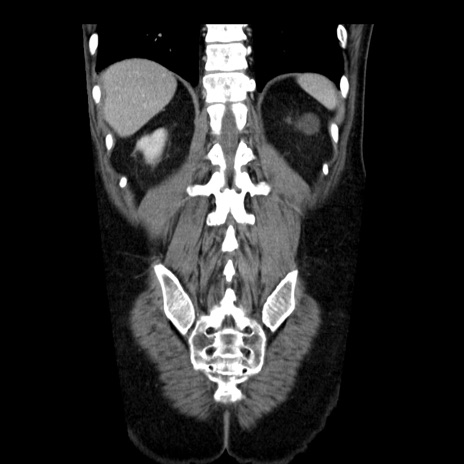

横断像

【症例】40歳代男性

【現病歴】2日前から胃痛あり。徐々に周期的な激痛に変化した。本日になっても激痛があるため受診。

【身体所見】意識清明、BT 38-39℃台あり、腹部:膨満、やや硬、右下腹部に圧痛あり。

【データ】WBC 8500、CRP 23.26